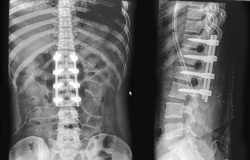

Le tour Cincom M532 est doté d’impressionnantes capacités multifonctions pour l’usinage de pièces à très haute valeur ajoutée, telles que vis orthopédiques, plaques ou rachis. Le travail avec ou sans canon est possible, avec un passage en barre jusqu’à 38mm. Le grappin d’éjection ainsi que l’éjecteur numérique apportent un gain de temps conséquent à l’éjection des pièces d’une longueur jusqu’à 280mm, comme les clous fémoraux, par exemple. Pour les outils entrainés, un entraînement individuel est à présent disponible. Le support vertical peut être équipé́, pour l’usinage de contour, d’un maximum de cinq axes pilotés, y compris axe B (type VIII). Le porte-outils pour l’usinage arrière dispose d’outils entrainés à réglage angulaire (types VII et VIII), ce qui lui permet de maîtriser les tâches d’usinage complexes en association avec l’axe Y.